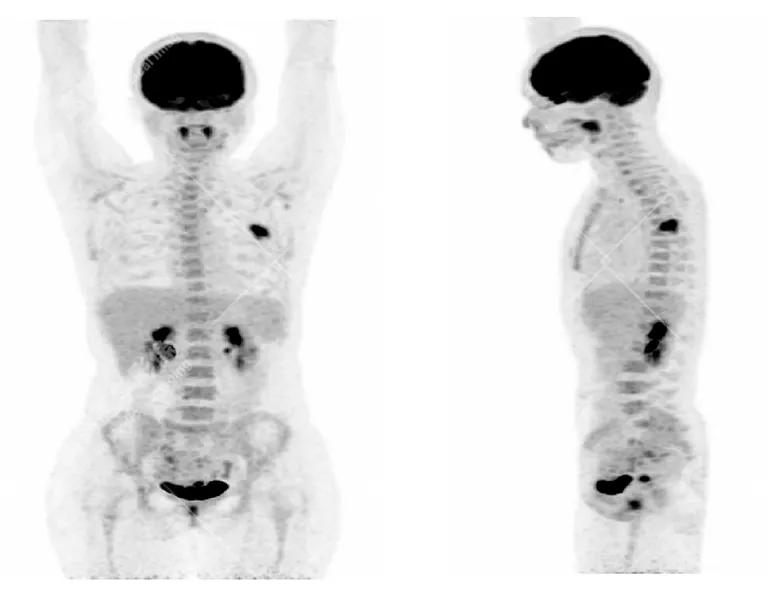

PET/CT

影像图

左胸一后肋溶骨性骨质破坏,周围伴软组织形成,FDG代谢增高,SUVmax为10.9。

找到引起骨痛病灶,病因:原发?转移?感染?

宫颈一片状稍低密度影,FDG结节样代谢增高,SUVmax为10.2。

最终诊断: 宫颈癌伴肋骨单发骨转移。